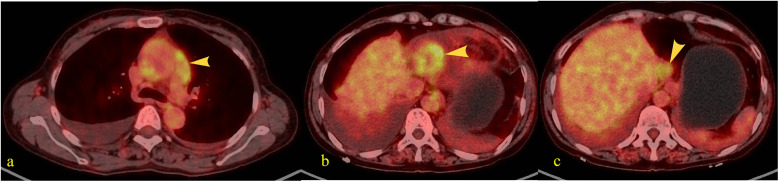

Cardiac tumors constitute an exceptionally rare neoplastic entity posing significant diagnostic challenges. We report a 55-year-old female patient without prior oncologic history who presented with acute-onset bilateral lower extremity edema progressing over 72 h. Transthoracic echocardiography demonstrated a pericardial mass with concomitant hemorrhagic pericardial effusion. Subsequent magnetic resonance imaging and systemic positron emission tomography localized the lesion to the right bottom of the heart. Surgical exploration suggested a cardiac occupancy as an irregular, fish-flesh-like soft tissue mass, pathology biopsy was performed suggesting a malignant tumour of epithelial origin, and immunohistochemistry was suggestive of hepatic origin. The patient received combination therapy comprising programmed death-1 inhibitor camrelizumab (200 mg via intravenous infusion every 21 days) and oral lenvatinib (8 mg once daily). Serial contrast-enhanced computed tomography of the thorax and abdomen demonstrated progressive metastatic dissemination with malignant pleural and peritoneal effusion formation. Despite therapeutic intervention, the patient ultimately experienced disease progression culminating in mortality.